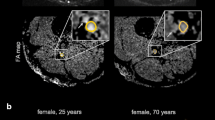

Image analysis was performed by two independent readers (M.K. and F.P. with more than 5 and 3 years of experience in neuromuscular imaging, respectively) using the DICOM-viewer OsiriX (Pixmeo Sarl, Bernex, Switzerland). Image quality was visually assessed by both readers and one participant was excluded in consensus due to severe motion artifacts, and thus the data of 27 participants were analyzed in this study. All analyses in this study refer to these 27 participants. A total of seven slices of interest were defined at mid-thigh to distal-thigh level in each scan in identical anatomical positions by F.P. and then used for independent segmentation by both readers. Segmentation of the sciatic nerve was performed in the anatomical T2-weighted image by freehand regions of interests (ROI) where nerve size and shape could be well-delineated (Fig. 2). Analysis of the sciatic nerve was restricted to the tibial portion to avoid inclusion of fat and connective tissue. The ROIs were then copied to the corresponding b0-image (b = 0) and slightly adjusted, mostly downsized, to avoid partial volume artifacts from surrounding fat tissue and to compensate possible distortion artifacts [19]. The FA, MD, AD, and RD were obtained using the OsiriX plugin DTI map with a preset noise threshold of 14. For further analysis, DTI parameters were averaged from all 7 slices.

Representative images of nerve segmentation. Segmentation of the tibial portion of the sciatic nerve was conducted independently by each reader using a free-hand ROI tool in OsiriX. ROIs were transferred onto co-registered DTI maps and slightly adjusted in the b0-image before DTI parameters were obtained. FA fractional anisotropy, MD mean diffusivity, RD radial diffusivity, AD axial diffusivity, T2w T2-weighted image